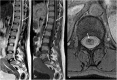

Background: Vascular lesions of the spinal cord are rare but potentially devastating conditions whose accurate recognition critically determines the clinical outcome. Several conditions lead to myelopathy due to either arterial ischemia, venous congestion or bleeding within the cord. The clinical presentation varies, according with the different aetiology and mechanism of damage.

Purpose: The aim is to provide a comprehensive review on the radiological features of the most common vascular myelopathies, passing through the knowledge of the vascular spinal anatomy and the clinical aspects of the different aetiologies, which is crucial to promptly address the diagnosis and the radiological assessment.